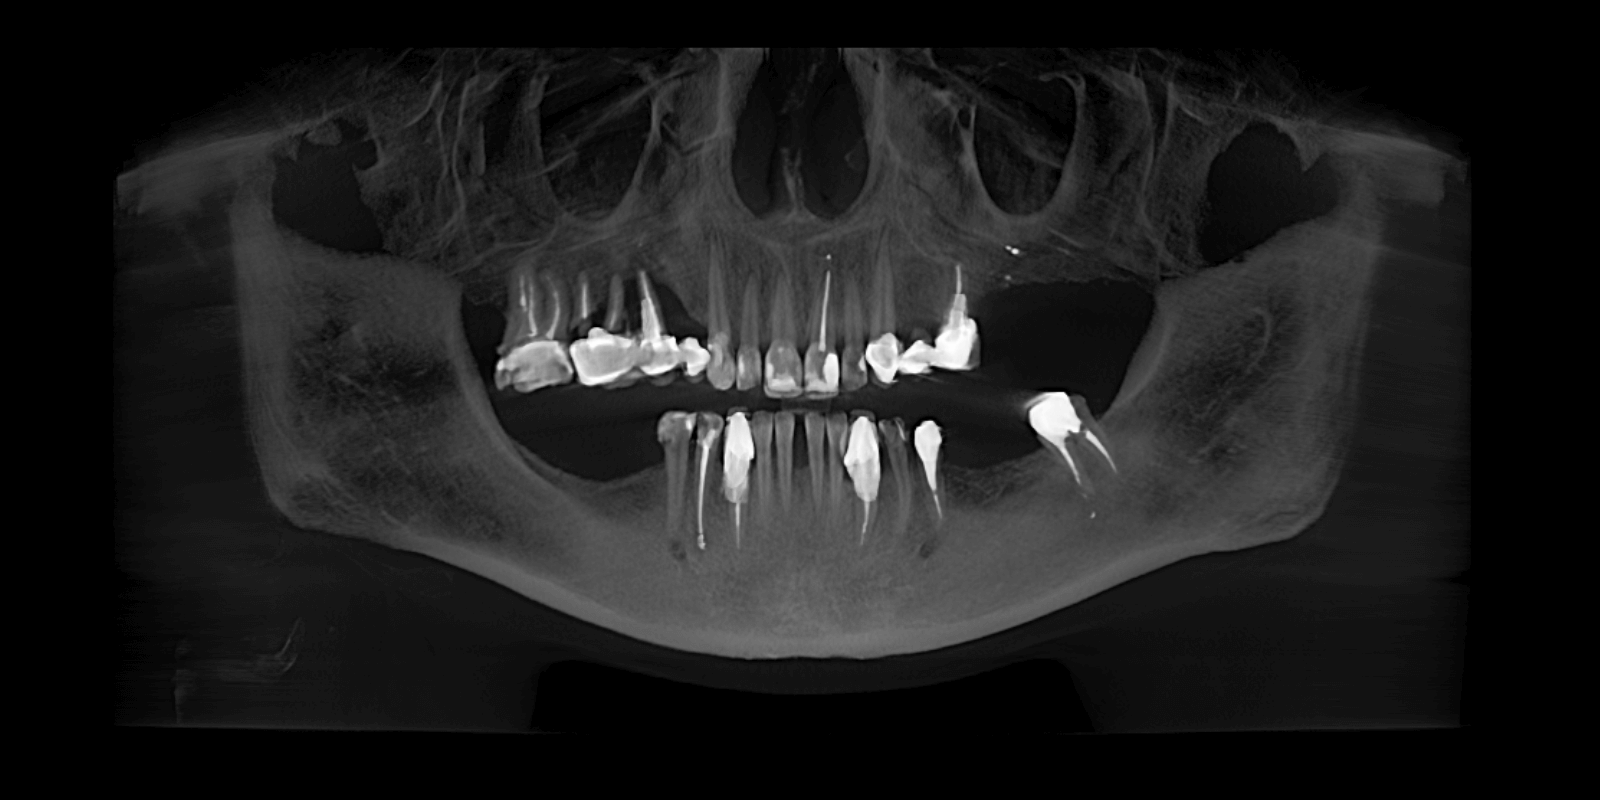

В нашу клинику обратилась женщина с многолетней усталостью в глазах. Она не могла нормально пережевывать пищу, стеснялась своей улыбки и постоянно подсознательно прятала лицо во время разговора. Ее беспокоили не только эстетические проблемы — отсутствуют зубы, старые мостовидные протезы, потемневшие пломбы, — но и функциональный дискомфорт, каждый день напоминавший о себе. Во время первичного осмотра (визуально) врач увидел:

- На верхней челюсти: 5 фронтальных зубов покрытых реставрационными пломбами, в области зубов 2.3-2.5 установлен металлокерамический мостовидный протез, 5 зубов отсутствуют. Установлен мостовидный протез в области зубов 1.4, 1.5, 1.6 с опорой на зубы 1.5 и 1.6. Зуб 1.7 покрыт металлокерамической коронкой.

- На нижней челюсти отсутствуют 5 зубов, передние зубы с большой тремой между ними, зубы 4.3 и 3.3 покрыты коронками из металлокерамики, на зубах 3.4, 3.5, 3.8 установлены большие корневые вкладки.

После осмотра врач направил пациентку на 3D КТ-исследование обеих челюстей, чтобы полноценно оценить состояние зубов и предложить обоснованный план лечения. На КТ был выявлен раскол корней зубов под мостовидным протезом на зубах 1.4-1.6.